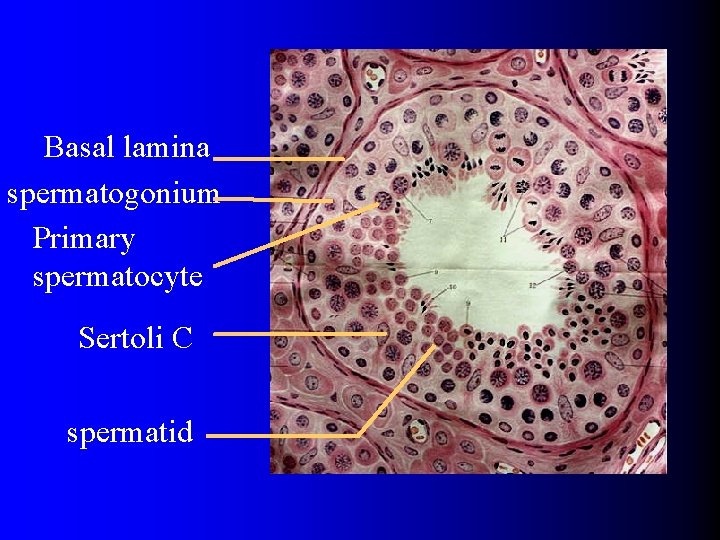

Basal lamina spermatogonium Primary spermatocyte Sertoli C spermatid

1. Spermatogenic cells • spermatogonium • primary spermatocyte • secondary spermatocyte • spermatid • spermatozoa spermatogenesis

(1)spermatogonium llocation: closely attach to basal lamina of spermatogenic Epi. l round,organells poorlydeveloped l differentiate into primary spermatocyte

(2)primary spermatocyte l attach to the luminal surface of the spermatogonia. l large. l after 1 st meiotic division, produce 2 secondary spermatocyte。

(4)spermatid l adjoining to the lumen. l No division,undergo extensive cell remodeling , as they differentiate into sperm. l this process is called spermiogenesis。

2. supporting C l Sertoli C. l stained lightly,nucleulus is obvious。 l sides with tightly junction. l support , nutrient spermatogenic cells.